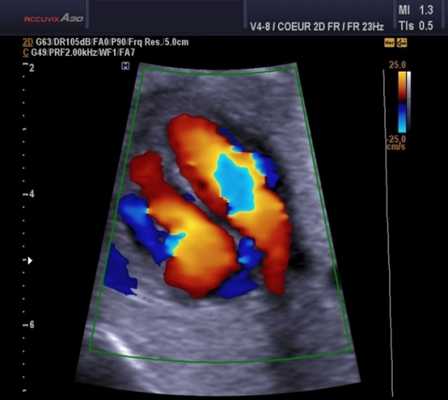

- Цветовая допплерография, при которой потоки, направленные в сторону датчика и от него, отображаются на экране различными цветами (в гамме соответственно от красного до синего). При этом зона ускорения кровотока представляется, по сути, количественным способом - путем отображения точек различного оттенка, что отражает наличие высокоскоростных потоков и феномена алайсинга.